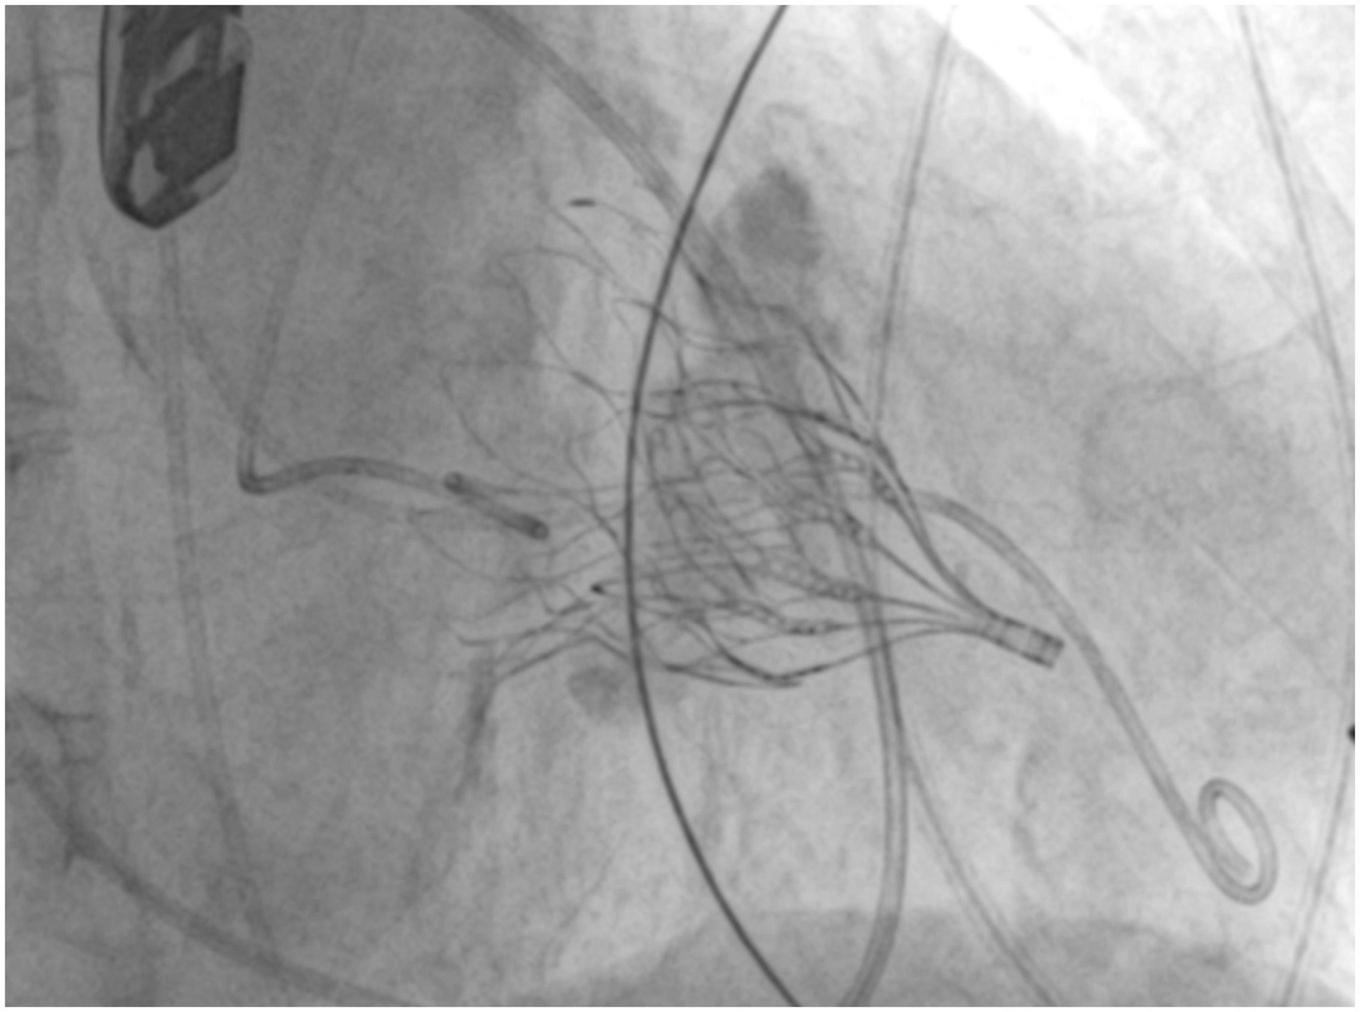

Gössl et al. (16) recently published early outcomes of TMVR with Tendyne in patients with severe MAC (Figure 4). Among 20 enrolled patients (9 compassionate use, 11 taken from the Feasibility Study of Tendyne in MAC), both acute and midterm outcomes were encouraging. In fact, 30-days all-cause mortality and 1-year cardiac mortality were 5 and 20%, respectively, with no recurrence of mitral regurgitation and clinical improvement in 92% of patients who were alive at 1-year follow-up.

FIGURE 4

Fluoroscopy image showing a successful Tendyne implantation in severe mitral annular calcification (MAC).